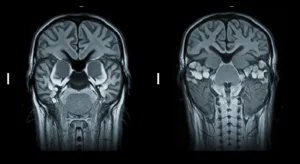

Look at this picture. It shows how PET and MRI use different ideas from physics to make treatments. They help doctors make good plans to treat cancer.

2. Magnetic resonance imaging (MRI) Scans

Magnetic resonance imaging is a procedure to make pictures of the inside of our body. It does not use X-rays; although, it relies on magnets and radio waves. Our body is mostly made of water and water has small parts like magnets. The big magnet on the MRI machine makes these small parts line up in a single direction. Then, the machine transmits radio waves that send these small parts. When they return to their original position, they emit their own radio signals.

The MRI machine hears such signals. One body part will report back different from another body part. This makes the machine draw a clear picture. Doctors can view tumors in position and watch how water and blood flow from it, thus knowing the tumor better. The pictures are changing with a slider for you to see. When the radio waves are altered, the picture looks changed, and it allows the doctors to see more about the tumor. Such imaging techniques are of great help in treatment plans. It is all diagnostic radiology.

Clearing images from medical scans is important for planning the best treatments. From the pictures taken during PET or MRI scans, that are powered by physics in cancer diagnostics. Doctors see the size and exact location of the tumor. High-tech computer tools are used to process this data. Medical physicists use these programs. Radiation oncologists use mathematics to design the best way to target the tumor. They find the most effective and safest way to direct the radiation. Experts direct the radiation at the tumor while ensuring that the healthy nearby tissues are exposed to only a low amount of radiation. Both doctors and physicists collaborate as a team. As a result, the best treatment plan is created for each patient. The picture illustrates how imaging leads to treatment.